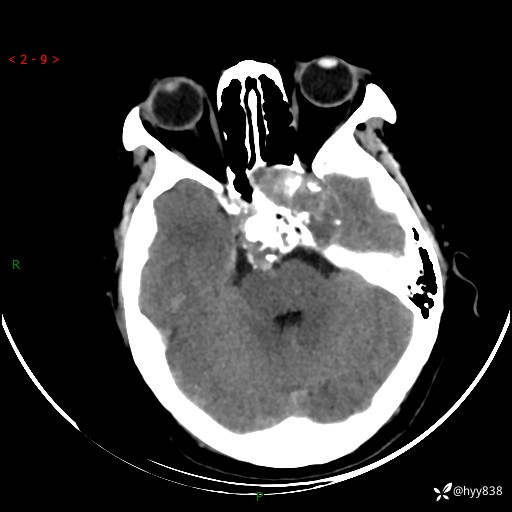

老年女性,视力下降3年。鞍区钙化性肿块,鉴别诊断有哪些---(有结果)

简要病史:患者3年前无明显诱因左眼出现视力下降,出现视物模糊,无头痛,无头晕,无恶心、呕吐,无意识障碍,无肢体麻木及抽搐,无心慌、胸闷,无腹痛、腹胀等不适,无旋地转感。个月前右眼视力下降,患者视物模糊逐渐下降,自诉看东西有雾感。在当地医院眼科就诊,症状无好转,行头部MR提示:鞍区肿物。现患者为求诊治来我科就诊,在当地市中医医院行头部CT:提示鞍区占位。患者现求进一步诊治来我院就诊,门诊以“鞍区肿物”收入我科。 患病以来,患者精神、饮食、睡眠尚欠佳,大小便如常,体力体重无明显变化。

临床诊断:鞍区肿物

颅脑CT平扫